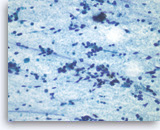

Metastatic small cell carcinoma of the lung,

Pancreas FNA, Cell Block.

The tumor cells with high nuclear to cytoplasmic ratios are present as structureless sheets. Tumor necrosis is present.

20X

Metastatic small cell carcinoma of the lung,

Pancreas FNA, Cell Block.

The tumor cells with high nuclear to cytoplasmic ratios are present as structureless sheets. Tumor necrosis is present.

20X